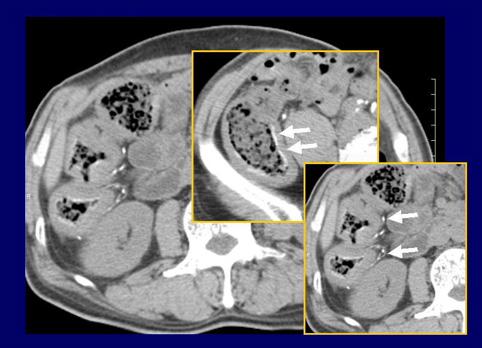

A case of idiopathic mesenteric phlebosclerosis (phlebosclerotic colitis).

Inflammatory or ulcerative disease / lesions/phlebosclerotic colitis

Large intestine(Colon)/More than one of the above

CT